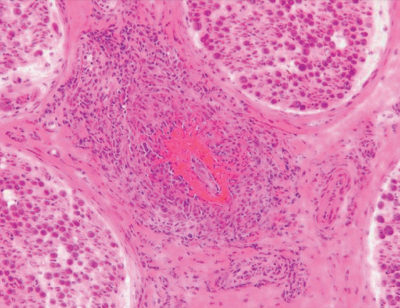

尿所見:蛋白 2+、糖 (-)、潜血 3+、沈渣に赤血球 50〜100/1視野、硝子円柱 1/数視野、尿蛋白 2.5 g/日。血液所見:赤血球 340 万、Hb 9.5 g/dL、Ht 32 %、白血球 17,700 (桿状核好中球 1 %、分葉核好中球 88 %、好酸球 1 %、好塩基球 1 %、単球 2 %、リンパ球 7 %)、血小板 16 万。血液生化学所見:総蛋白 5.0 g/dL、アルブミン 3.4 g/dL、尿素窒素 44 mg/dL、クレアチニン 2.6 mg/dL。CRP 14 mg/dL。右腓腹神経生検の H-E 染色標本を別に示す。